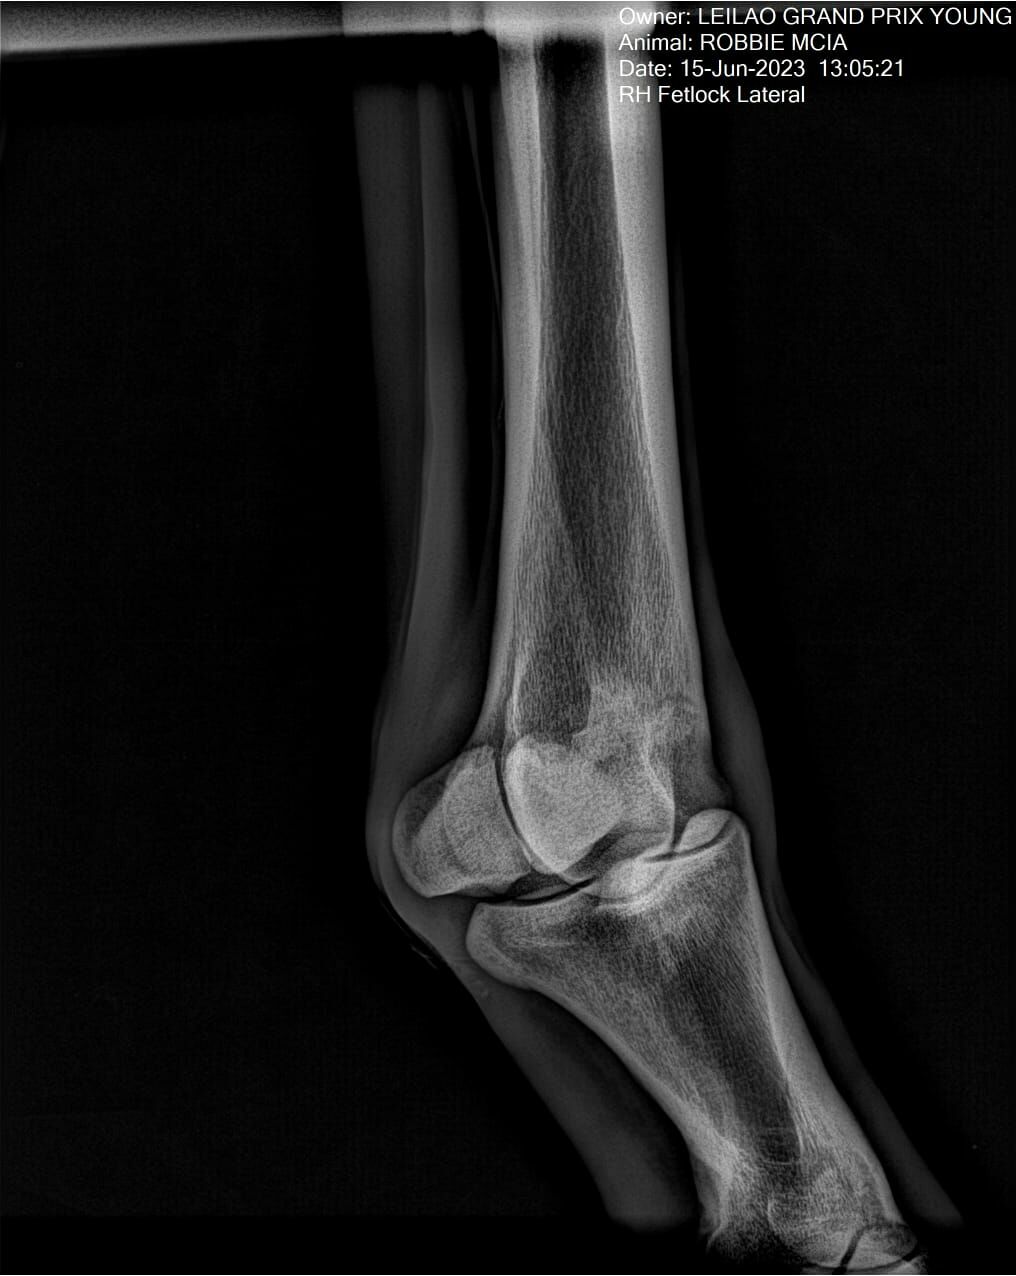

:: RAIOS-X DO LOTE